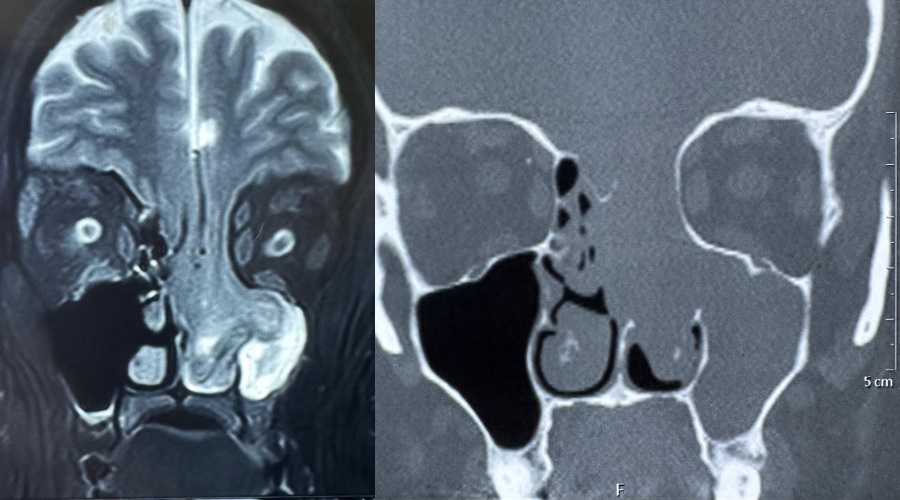

Dr. Ashish Vashishth, HOD & Consultant – ENT (Otorhinolaryngology, Head and Neck and Cranial Base Surgery, Ear, Nose and Throat) said, “When the patient came to us with persistent nasal obstruction, an initial endoscopic examination in our ENT department raised suspicion of a rare condition. Targeted CT and MRI scans revealed that part of her brain had herniated through the eroded skull base into the nasal cavity. This case certainly highlights the importance of a thorough diagnostic pathway and consulting the right specialists at the right time. What made this case challenging was the technical precision needed to manage such a delicate and high-risk cranial base reconstruction. The success of this case truly highlights the strength of a multidisciplinary and diagnostic-first approach.”

Dr. Anurag Saxena, Cluster Head-Delhi NCR, Neurosurgery, said, “This was an extremely rare and technically demanding case. The patient was at significant risk of developing a life-threatening stroke, as the brain’s blood vessels were also herniating down along with the brain tissue. Even the slightest injury to these vessels could have caused devastating complications. Almost half of the frontal and basal parts of the brain were hanging down through the skull base defect, which made performing the surgery exceptionally complex. Through a carefully coordinated endoscopic and transcranial approach, we successfully repositioned the brain, reconstructed the skull base, and ensured her safe recovery. The patient has now recovered well and is leading a normal life under regular follow-up care.”